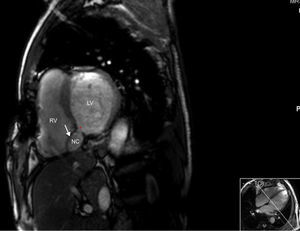

Although the patch significantly reduced the interventricular communication, a residual defect remained, with turbulent left-to-right shunt, draining into a cavity that corresponded to the aneurysmal dissection of the septum, and that communicated distally with the right ventricle (Figure 2), findings confirmed by cardiac magnetic resonance imaging (Figures 3 and 4).

Cardiac magnetic resonance gadolinium perfusion imaging. Immediately after contrast injection, flow can be seen from the left ventricle into the cavity formed by the interventricular septal dissection, which finally drains into the apical region of the right ventricle. LV: left ventricle; NC: neocavity formed by the dissection of the interventricular septum; RV: right ventricle. Asterisk: residual ventricular septal defect.